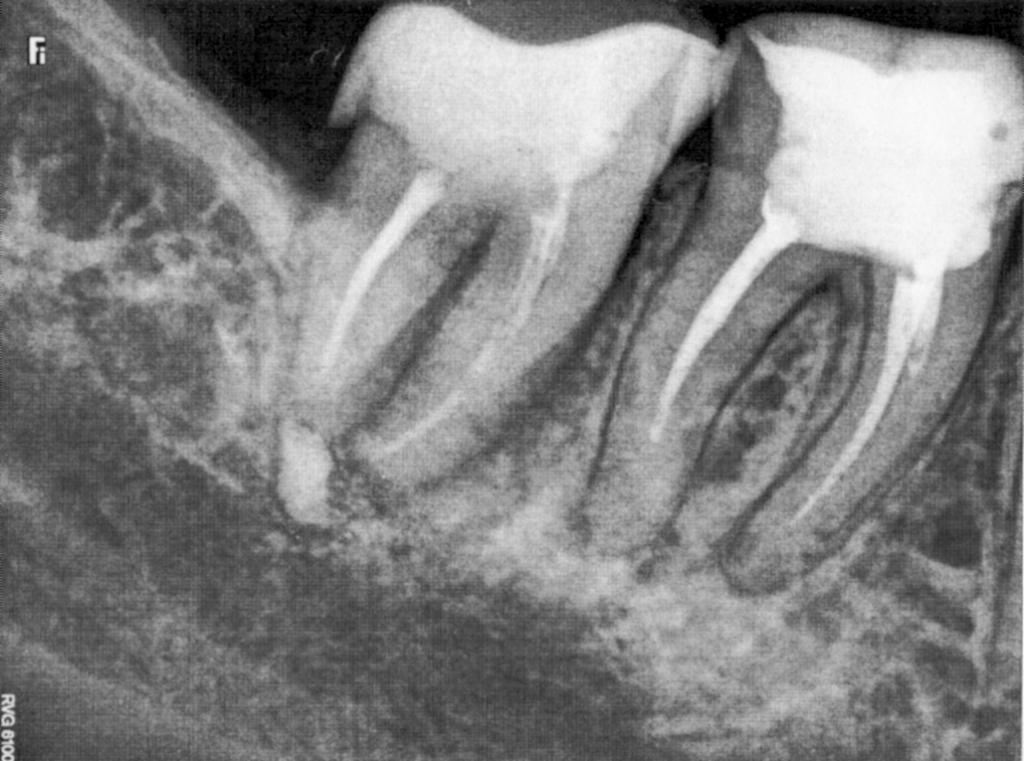

Помогите, пожалуйста! Есть проблемы с 7-кой: после еды появляется боль пульсирующего характера, при постукивании во время осмотра и если не есть на этой стороне, - боли нет. Соседняя 6-ка неоднократно пломбирована, при потере 7-ки может тоже "полететь". Мнения врачей в отношении тактики лечения разделились.

Хотелось бы определенности: можно ли вылечить? Каков прогноз?